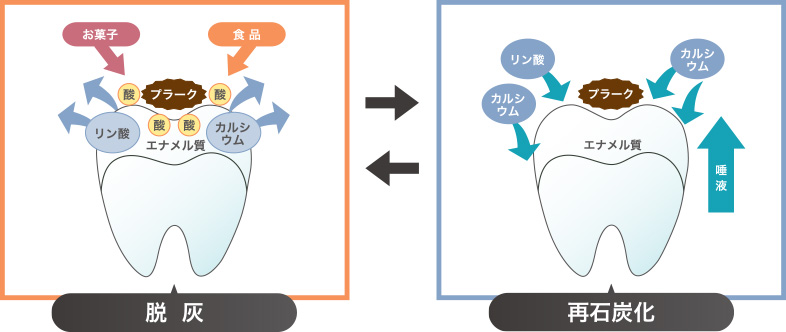

食後、時間の経過とともに、食べ物が口に入ってきた影響により、酸性に傾いたお口の中では、歯のエナメル質からカルシウムやリンがどんどんと溶け出す「脱灰(だっかい)」という現象が起きますが、だ液が持つ中和する働き(緩衝能)により、徐々にpHが元に戻ります。さらに、「再石灰化(さいせっかいか)」といい、だ液の中に含まれているエナメル質と同じ成分のカルシウムやリンが、食事をするたびにお口の中で「脱灰」と「再石灰化」が繰り返し行われています。

このように歯は、日々、脱灰と再石灰化を繰り返しておりますが、プラークの停滞や、間隔を開けずに飲食をすることで酸性の状態が長く続いてしまい、再石灰化するまもなく進行し、ついには再石灰化では元に戻ることが出来ない「不可逆性のむし歯」になってしまいます。